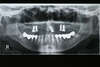

Cas n° 9

Patient venu consulter afin de supprimer sa prothèse partielle amovible du bas de 7 éléments

Solution :

- 1 bridge classique de 4 éléments a été réalisé, coté gauche.

- 1 implant au niveau antérieur a été posé afin de réaliser 2 éléments scellés sur cet implant.

-1 implant a été posé coté droit avec une couronne coulée transvissée dur l'implant